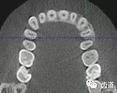

1、上頜尖牙阻生

上頜尖牙埋伏阻生在CBCT中的影像

2、下頜磨牙阻生

下頜第二第三磨牙阻生口腔曲面斷層片影像

下頜第二第三磨牙阻生CBCT影像定位

三種圖片的影像學(xué)比較